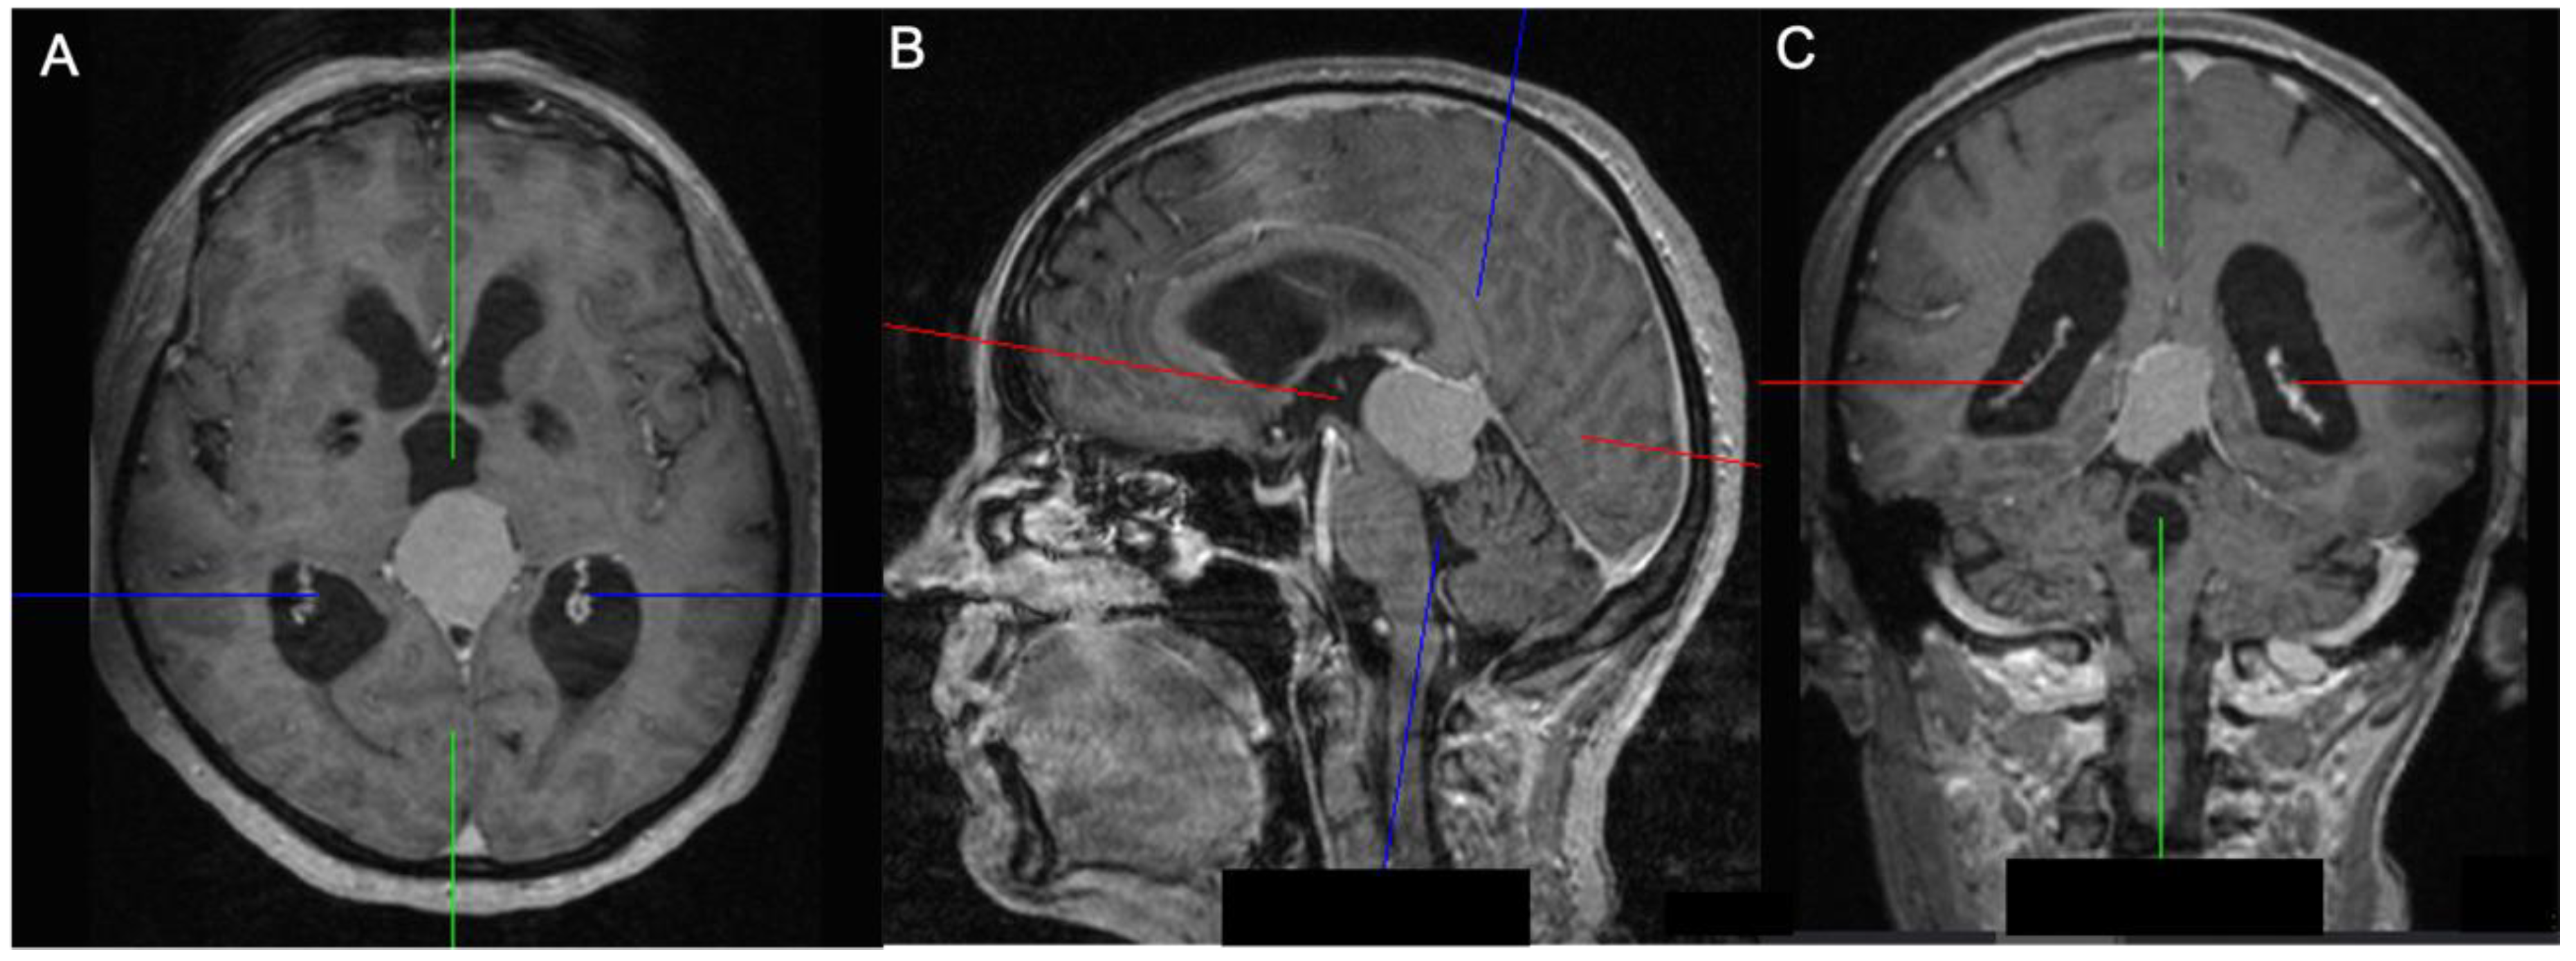

2.2. Volumetric Analysis, Vascular Features, and Tentorial Angle

3.2. Preoperative Imaging Data

| Radiological data | Preoperative tumor volume (cm3) | 17.8 (±17.2) |

| Preoperative tumor edema (cm3) | 21.9 (±38.0) | |

| Infiltration of the straight sinus | 1 | |

| Infiltration of the superior sagittal sinus | 2 | |

| Displacement of the straight sinus | 5 | |

| Displacement of the vein of Galen | 4 | |

| Hydrocephalus | 4 | |

| Tentorial angle | 49.6 (±6.2) | |